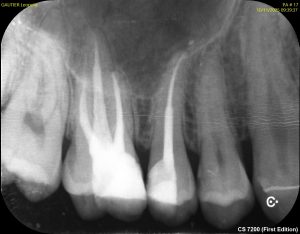

radiographie montrant les dents dévitalisées